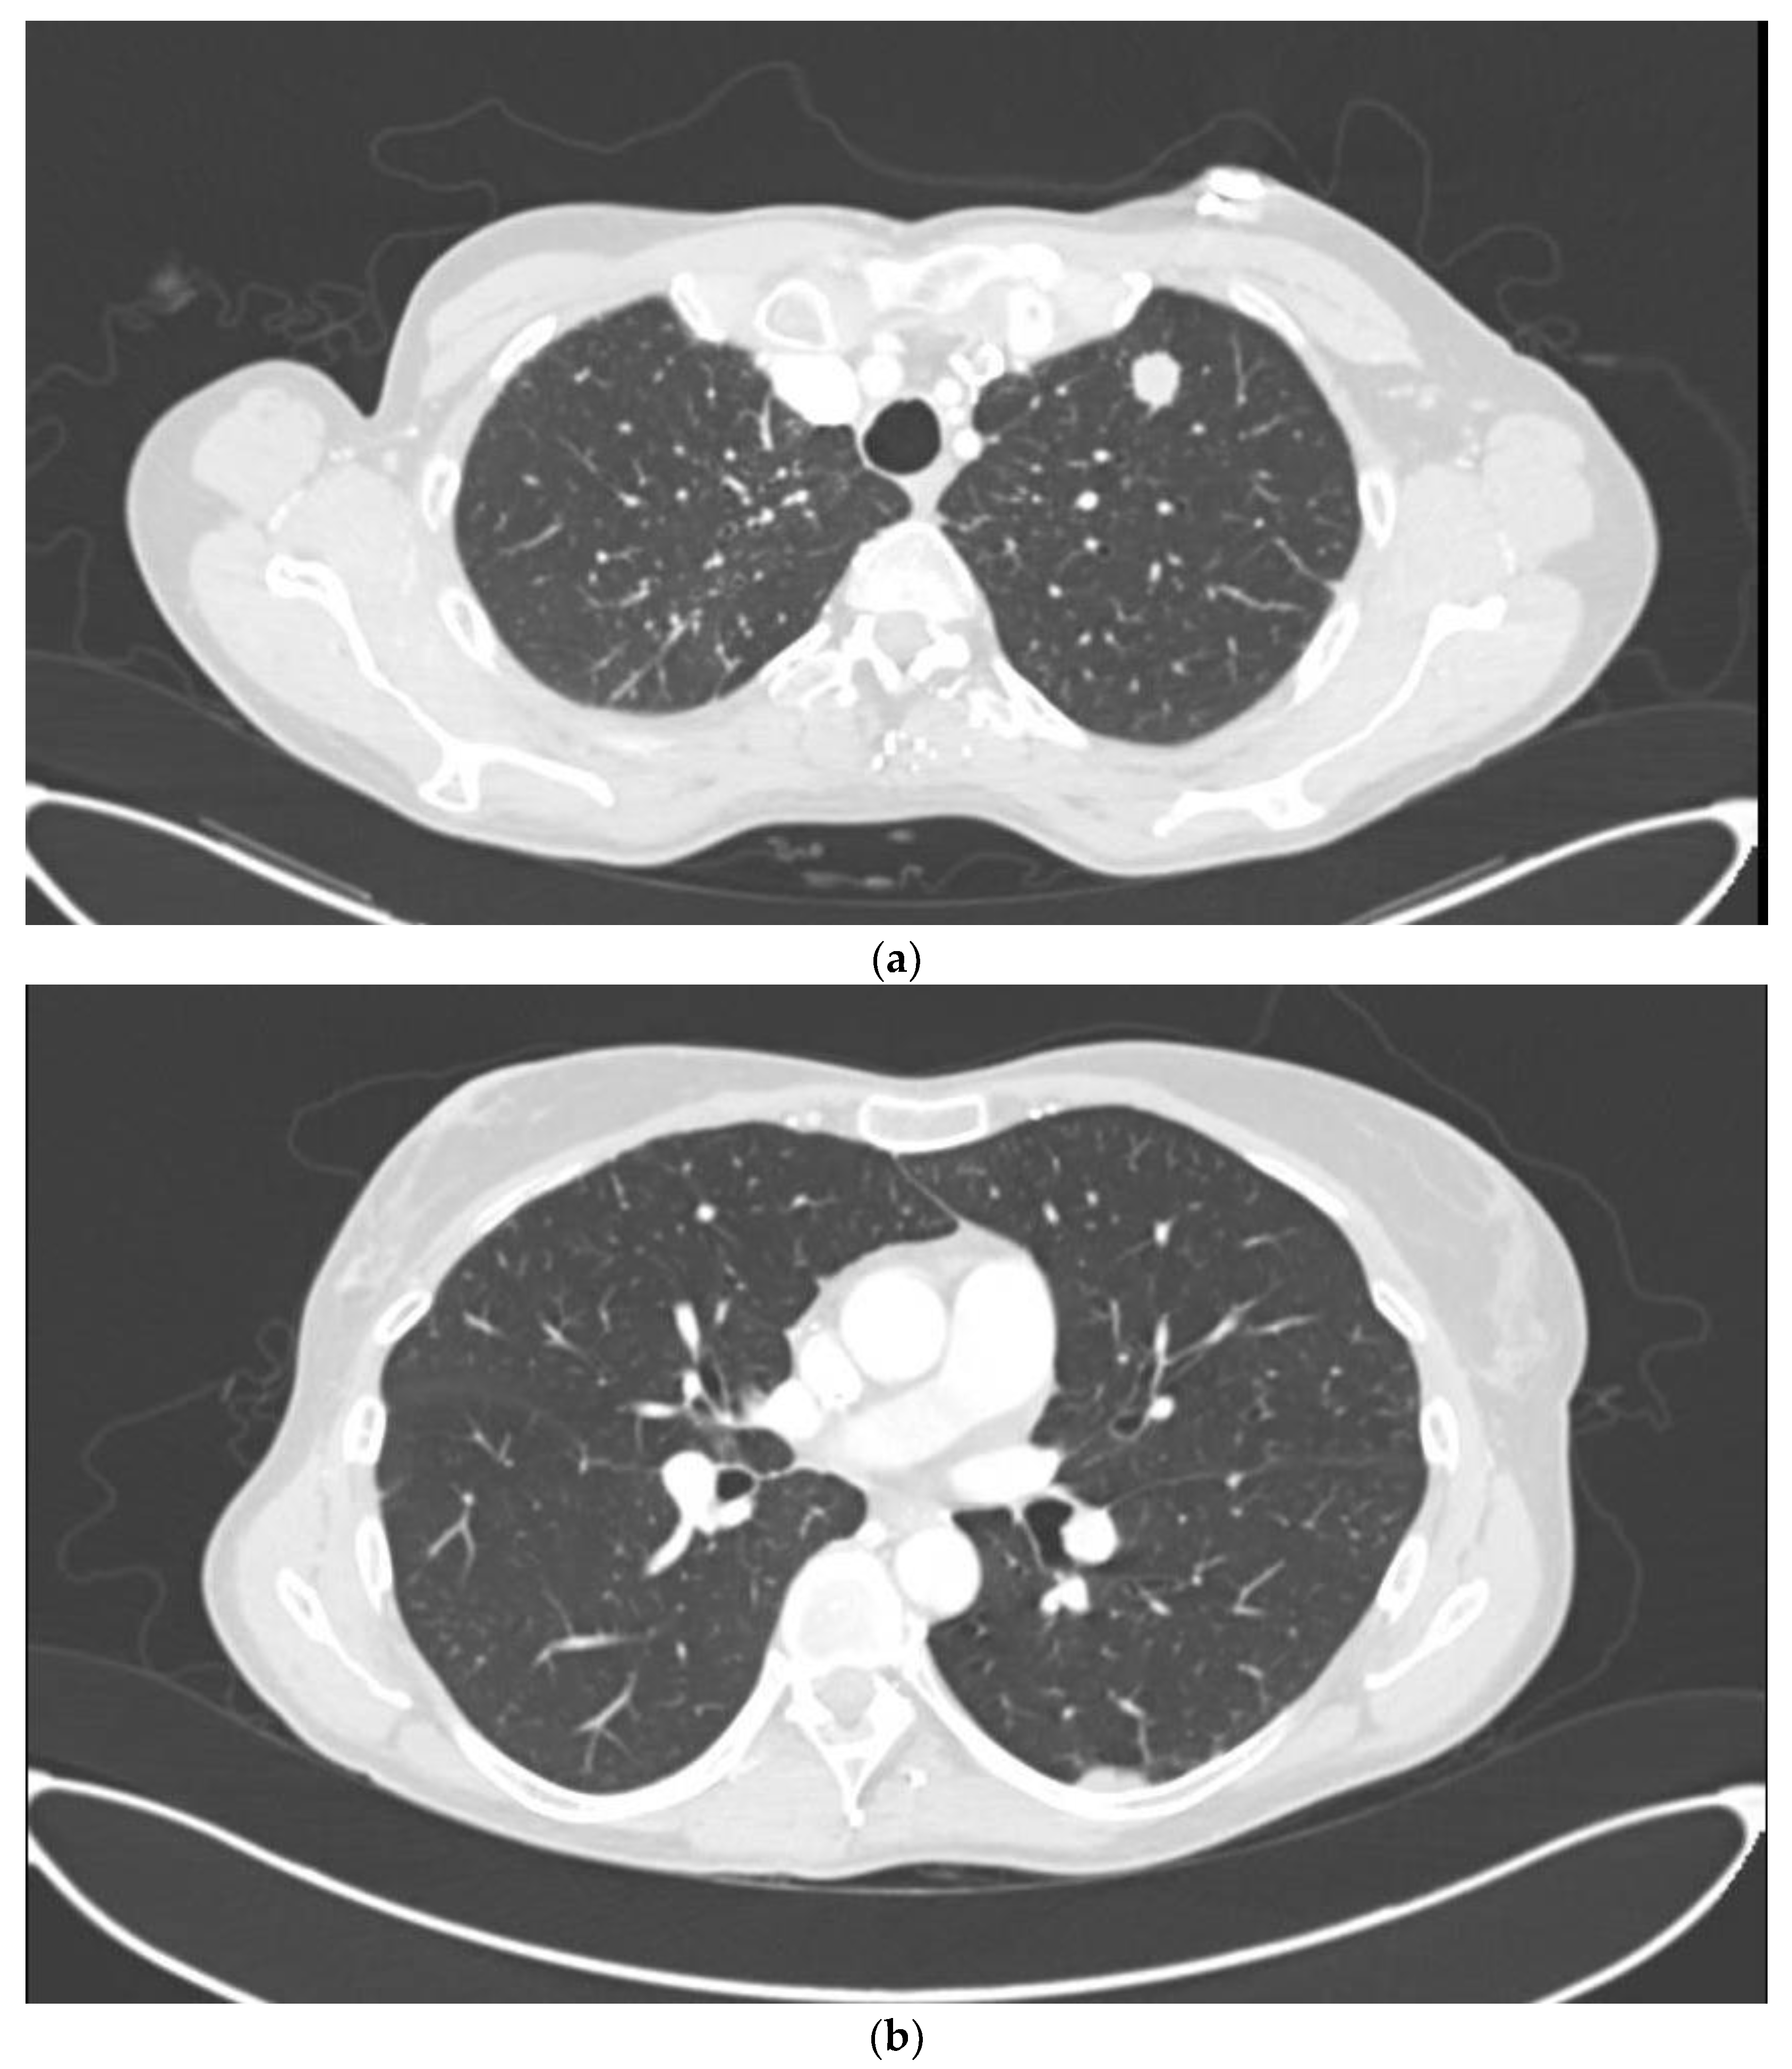

| Lung | 3 pts (5.1%) | |

| Lung RT treatments | SBRT 50 Gy in 5 fr | 3 pts (100%) |